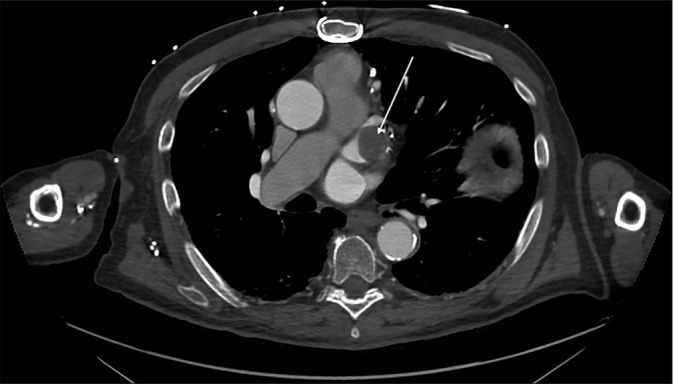

Saphenous vein graft aneurysm (SVGA) is a rare but potentially life-threatening complication of coronary artery bypass grafting (CABG). Its incidence is likely underreported due to asymptomatic cases and undiagnosed acute events. While SVGAs are more commonly associated with right atrial compression, presentation as a left atrial mass is rare. We present the case of an 85-year-old man with a history of CABG, who was incidentally found to have a left atrial appendage (LAA) density on a computed tomography (CT) chest, abdomen, and pelvis performed for unrelated symptoms of back pain and constipation. The density was initially suspected to be an LAA thrombus. However, a dedicated cardiac CT with delayed-phase imaging revealed a largely thrombosed aneurysmal saphenous vein graft to the obtuse marginal artery, which indented the LAA, mimicking an intracardiac mass. This case underscores the critical role of multimodality imaging, particularly cardiac CT, in differentiating vascular aneurysms from true intracardiac masses. Given the patient's asymptomatic status, conservative management with close follow-up was pursued. This case adds to the limited literature on SVGAs mimicking left atrial pathology and highlights the importance of recognizing this rare entity to avoid unnecessary interventions. It also emphasizes the evolving role of cardiac CT as a noninvasive, high-yield diagnostic tool for complex post-CABG anatomical assessments.

Abstract Image